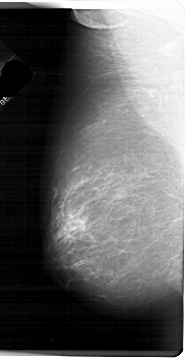

A_1739_1.RIGHT_CC

RIGHT_CC LINES 6121 PIXELS_PER_LINE 3136 BITS_PER_PIXEL 12 RESOLUTION 43.5 OVERLAY

FILE: A_1739_1.RIGHT_CC.OVERLAY

TOTAL_ABNORMALITIES 1

ABNORMALITY 1

LESION_TYPE MASS SHAPE LOBULATED MARGINS CIRCUMSCRIBED

ASSESSMENT 3

SUBTLETY 1

PATHOLOGY BENIGN

TOTAL_OUTLINES 1

BOUNDARY